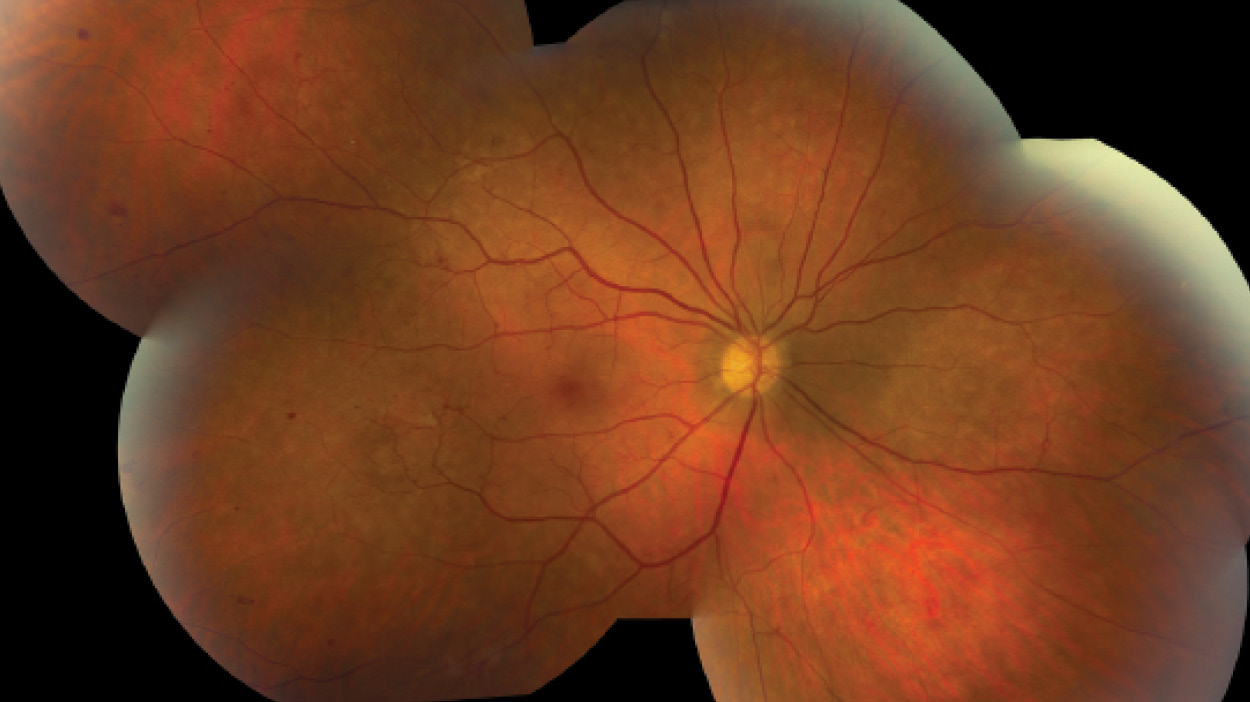

A 46-year-old white man presented with decreased VA of 20/30 in his right eye and 20/25 in his left eye associated with headaches. Dilated fundus examination revealed bilateral optic disc neovascularization, white-centered retinal hemorrhages, venous dilation with areas of telangiectasis, and retinal neovascularization (Main Image). The patient had an elevated white blood cell count of 243.9 K/µL (normal: 4.3-5.7 K/µL) and a hemoglobin level of 7.9 g/dL (normal range, 13.8-17.2 g/dL).

Despite good control of systemic disease, CML retinopathy progressed, with recurrent preretinal and vitreous hemorrhages in each eye (Insets, left and middle). Bilateral full panretinal photocoagulation was performed, followed by pars plana vitrectomy with membranectomy, endophotocoagulation, and gas-air exchange (16% C3F8) in each eye. Final VA is 20/25 in each eye with no signs of active retinopathy (Inset, right). The patient continues to be in remission of CML.